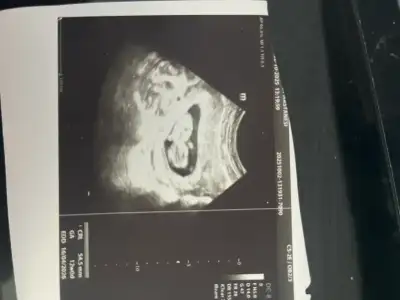

Arkadaşlar merhaba daha önce burada ultrason fotoğrafına bakıp cinsiyet tahmin edenleri görmüştüm benim içinde bi heyecan olur:) var mıdır tahmininiz normalde 12+4 üm ama ultrasonda 13 haftalık görünüyor